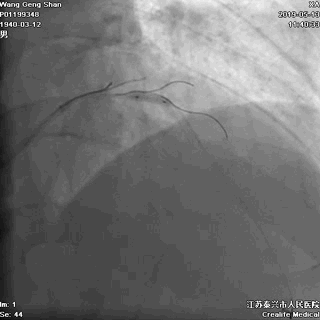

03 第一第二对角支保护

对角支导丝到位

左冠共计5根导丝

前降支近段支架植入后用非顺应性球囊高压扩张